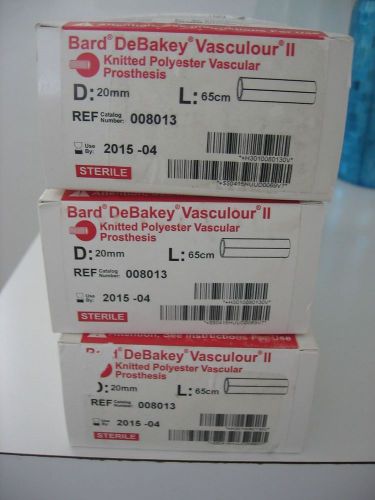

Vascular graft Bard DeBakey Vasculour Implant Aortic knitted graft Lot of 3